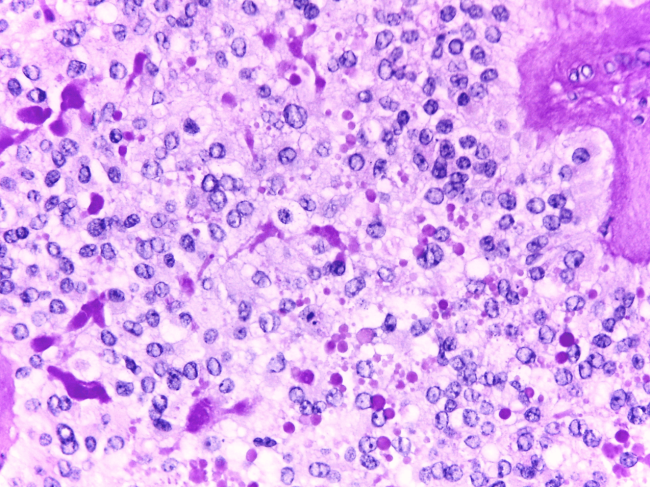

- Anatomia Patológica

Os meios de diagnóstico protocolados para a confirmação dos tumores dos digestivo alto são:

- Endoscopia digestiva alta

- Biópsia gástrica

No caso dos tumores hepatobiliopancreáticos, estão prorocolados os seguintes meios complementares de diagnóstico:

- Biopsia hepática

- Biopsia aspirativa percutânea